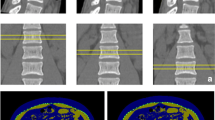

DXA (QDR 4500A; Hologic, Waltham, MA, USA) was performed to measure the BMD of the proximal femur (femoral neck) and lumbar spine (L2-L4) by an experienced and qualified radiographer (Fig. 1). By the definition from the World Health Organization, a BMD T-score of −2.5 or below is diagnosed as osteoporosis.